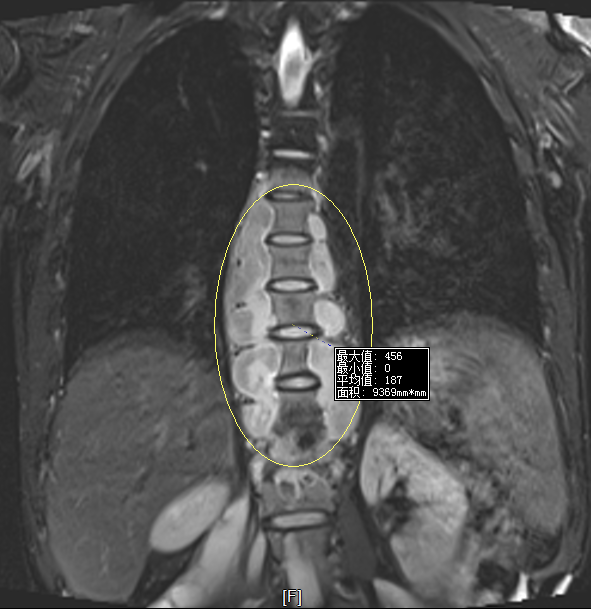

(通訊員  張保亮)小強(qiáng)(化名),男,32歲,永州人,近2年來(lái)覺(jué)得全身乏力,食欲下降,尤其是近半年來(lái)腰背部,臀部及大腿多處脹痛,在當(dāng)?shù)囟嗉裔t(yī)院就診,被診斷為骨結(jié)核,經(jīng)過(guò)1年多的治療,病情無(wú)好轉(zhuǎn)逐漸加重。1個(gè)月前經(jīng)人介紹來(lái)到永州市中心醫(yī)院北院,脊柱外科主任張勇主任醫(yī)師接診了該患者,仔細(xì)詢問(wèn)病人情況并檢查后發(fā)現(xiàn)該患者確實(shí)是患上了胸腰椎結(jié)核合并全身多發(fā)巨大流注膿腫,由于該患者近2年來(lái)四處求醫(yī)問(wèn)藥,治療很不規(guī)范,造成病情逐漸發(fā)展,脊柱死骨形成,多處巨大膿腫形成,抗癆藥也出現(xiàn)耐藥,治療起來(lái)十分棘手。如果不給予有效治療,該患者將面臨癱瘓甚至死亡的風(fēng)險(xiǎn)。

術(shù)前